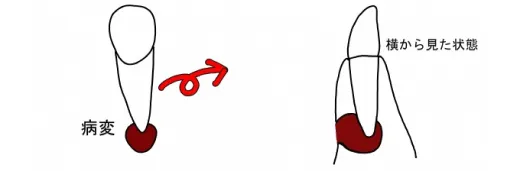

CT撮影では何が分かるのか?

1.重なり合って分からなかった病変の原因を特定できる

2.骨が溶けている範囲が骨に囲まれているか否かを判別できる

3.歯の根が折れているのかどうかを骨の溶け方から推察できる

4.根の先が神経や上顎洞からどのくらい離れているのか診断できる

5.埋伏している歯がどこにあるか正確に分析できる